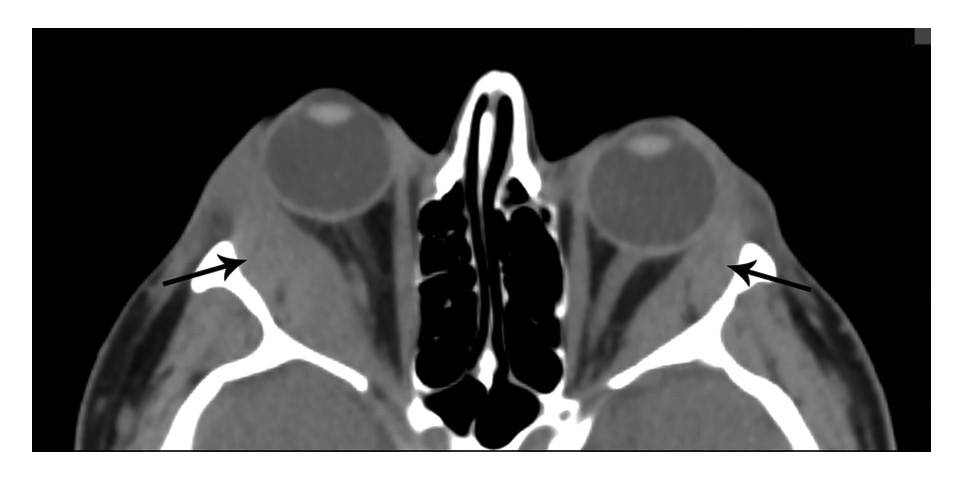

Через 6 мес после начала ухудшения отметила появление выраженного экзофтальма, болей в проекции правой орбиты, слезотечения, отеков век. Концентрация тиреоидных гормонов была в пределах нормы (ТТГ 1,22 мМЕ/л, свободного Т4 12,5 пмоль/л), содержание антител к рецептору ТТГ составляла 0,3 МЕ/л. Отмечались небольшое превышение содержания антител к ТПО до 22,7 МЕ/м (при норме до 5,6 МЕ/м), увеличение объема ЩЖ до 21 см3, умеренное снижение эхогенности с множественными мелкими гипоэхогенными зонами, неизмененная васкуляризация. При объективном исследовании обращали на себя внимание отек век, более выраженный справа, расширение эписклеральных сосудов, двусторонний экзофтальм, более выраженный справа (правый глаз (OD) 26 мм, левый глаз (OS) 22 мм), затруднение репозиции глазных яблок, вторичное косоглазие слева, нечеткость границ зрительного нерва при офтальмоскопии (рис. 1). Проведена МСКТ орбит: КТ-картина выраженного экзофтальма, утолщения глазодвигательных мышц (наружной и нижней прямых), значительное увеличение слезных желез (справа 30,0×15,8 мм, слева 25,0×11,5 мм, при норме: длина 5,4–12,9×2,7–6,5 мм), структура однородная, плотность снижена: справа 52 НU, слева 52 НU, признаки апикального сгущения справа (рис. 2).

Рис. 2. МСКТ орбит (аксиальная проекция) до лечения. Выраженное утолщение наружной прямой мышцы, увеличение слезных желез (стрелки).

Рис. 10. КТ орбит (аксиальная проекция) на сроке лечения 10 мес. Значительное уменьшение поперечника наружных прямых мышц и слезных желез (стрелки).

В результате иммуносупрессивного лечения отмечена выраженная положительная динамика: уменьшение экзофтальма, ретракции нижних век, регрессия косоглазия, бинокулярного двоения и периорбитальных отеков (рис. 9, 10). Лагофтальм на правом глазу не регистрируется. На сроке наблюдения 10 мес ремиссия воспалительного процесса в орбите сохранялась на поддерживающей дозе глюкокортикоидов.